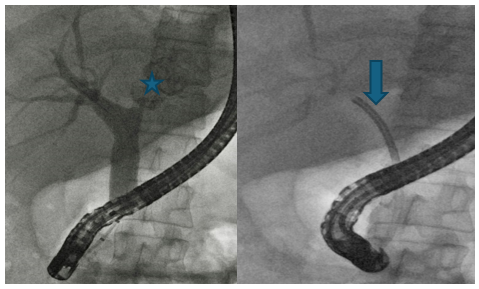

The maximum provocation method was used to examine 60 patients, with a slight predominance of women (55%). Except for 3 patients under the age of 20 years, the remaining patients were aged from 53 to 76 years (62 ± 4). All patients had GERD symptoms that they could not control, including 53 patients who received PPI. In 39 cases, patients underwent endoscopy from 1 to 4 times. In only one case, erosion was found in the esophagus, the benign nature of which was confirmed by histological examination. A small diaphragmatic hernia was described in two patients. In 18 patients, gastritis was diagnosed with endoscopy. Thus, only one of 39 patients was diagnosed with erosive esophagitis, confirming the diagnosis of GERD. In 38 (97%) patients, endoscopic examination without histology did not reveal evidence in favor of GERD. Even though taking PPI did not relieve patients from debilitating symptoms, only 2 patients were referred for pH monitoring. Each of them had a DeMeester score below 4. Analysis of medical history revealed a surprising pattern. The disease always began with heartburn. After some time, pain syndrome was recorded more often, from a pressing feeling behind the sternum to pain in the epigastrium. Heartburn occurred only after eating excess food. Despite occasional heartburn, abdominal pain, or belching, patients considered themselves healthy for a long period. In some patients, symptoms returned after many years and more often than in the early period, extraesophageal symptoms (hoarseness or alteration of voice, sensation of foreign body in throat, importunate cough, etc.) were bothered. Figure 5 provides examples of low pain sensitivity of the esophagus with complete incompetence of the LES (chalasia of EGJ).

Figure 5. Radiographs of patients with chalasia EGJ. (a-b). A 68-year-old woman has been ill since her youth, when   heartburn appeared. She was diagnosed with asthma when she was young. The bronchospasm attacks passed. Recently, small   amount of milk in coffee causes severe heartburn after 15-30 minutes. She takes 20 mg of PPI per day, which is enough   to prevent heartburn. Repeated endoscopy always revealed only a “hiatal hernia.” (a). During maximum provocation, a   sharp dilation of the esophagus is visible, especially in its ampullary region, as well as a sharp dilation of the esophageal opening of the diaphragm. (b). After 5 minutes, free reflux from the stomach into the esophagus is determined. (c-d). A 72-year-old man complained of a debilitating cough, change in voice, and a sensation of a foreign body in the throat for 4   months. Very rarely small pieces of food appear in the mouth. For a month he woke up at night because he is choking on   saliva. He does not feel any acid or bitterness in his mouth. He has no heartburn, pain, or dysphagia. About 15 years ago   he had heartburn, which went away only after swallowing a tablet with a diameter of about 3 cm. Since then, he considered himself healthy. (с). A sharp shortening of the LES (1 cm), expansion of the esophageal ampulla and   symmetrical narrowing of the esophagus at the level of the aortic arch (arrow) are detected. (d). After 5 minutes, free   reflux of barium from the stomach into the esophagus is determined. The patient swallowed a tablet with a diameter of 1.9 cm. After this, he stopped choking on saliva at night. This is a typical example of the formation of a functional sphincter (AES) over the aortic narrowing of the esophagus.

These typical cases show that (1) in the process of ontogenesis, the clinical symptoms of GERD can change significantly; (2) over time the esophagus loses pain sensitivity, which can be explained by the damage to the sensitive elements in the esophageal mucosa by the gastric juice; (3) lactose triggers GERD symptoms without reaching the colon. Symptoms are felt more quickly with chalasia of EGJ, since excess hydrochloric acid, as soon as it appears in the stomach, immediately enters the esophagus.